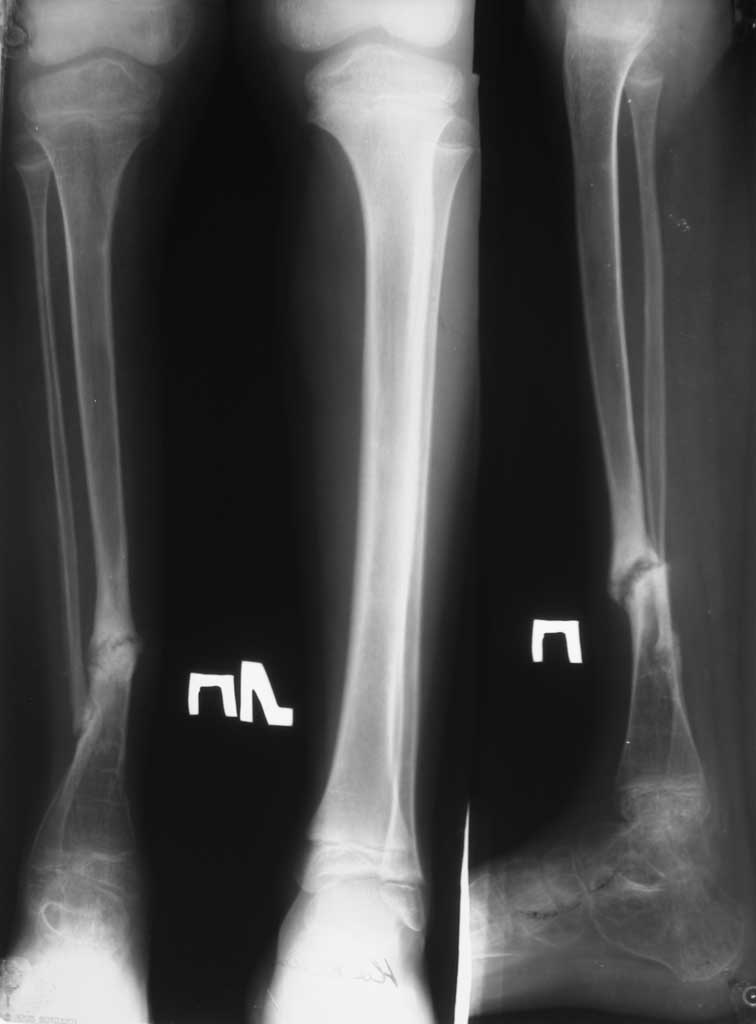

Больной 11 лет. Врожденный ложный сустав нижней трети правой большеберцовой кости.

Больной оперирован неоднократно в областных и республиканских центрах. Прошу о вашей тактике лечения данного больного. Моё мнение: резекция малоберцовой кости в области нижней трети, аккордионной метод компрессии. И дистракция, закрытая кортикотомия верхней трети большеберцовой кости апаратом Илизарова Латиф